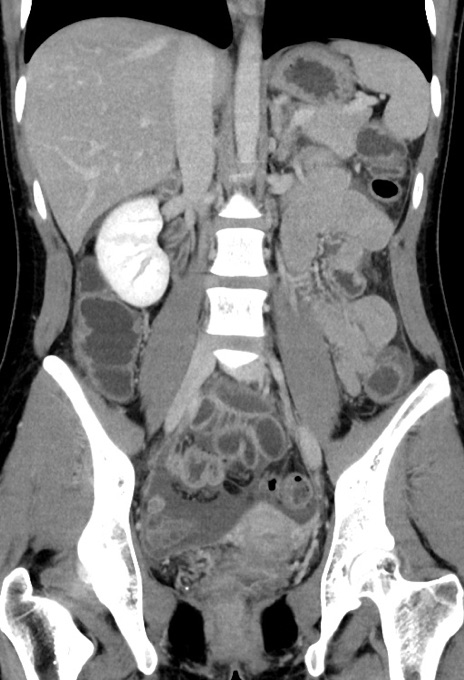

症例17(冠状断像)

【症例】20歳代女性

【主訴】嘔吐、下腹部痛

【現病歴】昨日夕食後に嘔吐し下腹部痛が出現。本日になっても嘔吐持続し改善しないため来院。

【身体所見】意識清明、BT 37.2℃、BP 108/67mmHg、腹部:平坦、やや硬、下腹部正中から右にかけて圧痛あり、反跳痛軽度あり、tapping pain(+)。

【データ】WBC 13600、CRP 14.94